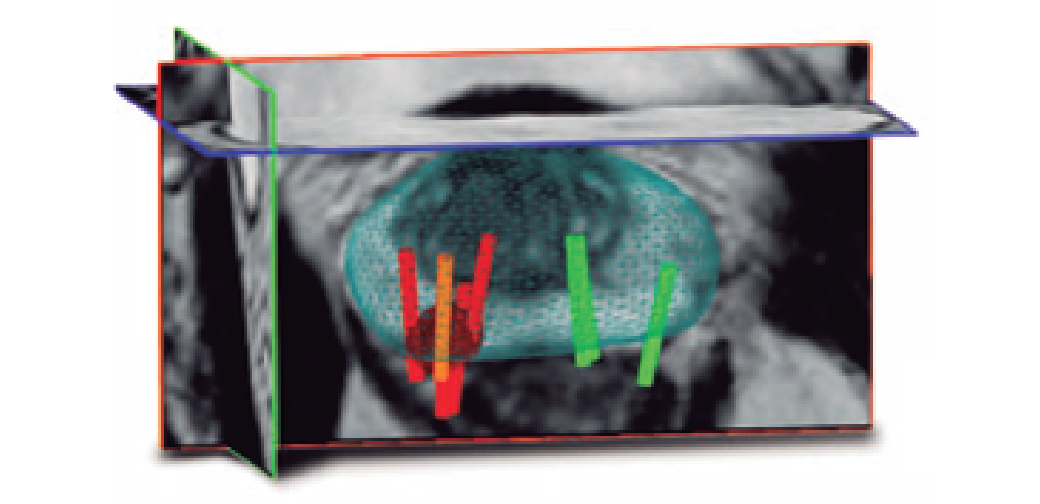

MRI融合活检

通过 MRI 和 3D 回波的融合,我们可以可靠地对高度怀疑癌症的区域进行活检。这肯定会提高MRI阳性病例的诊断率并降低再次活检的风险。